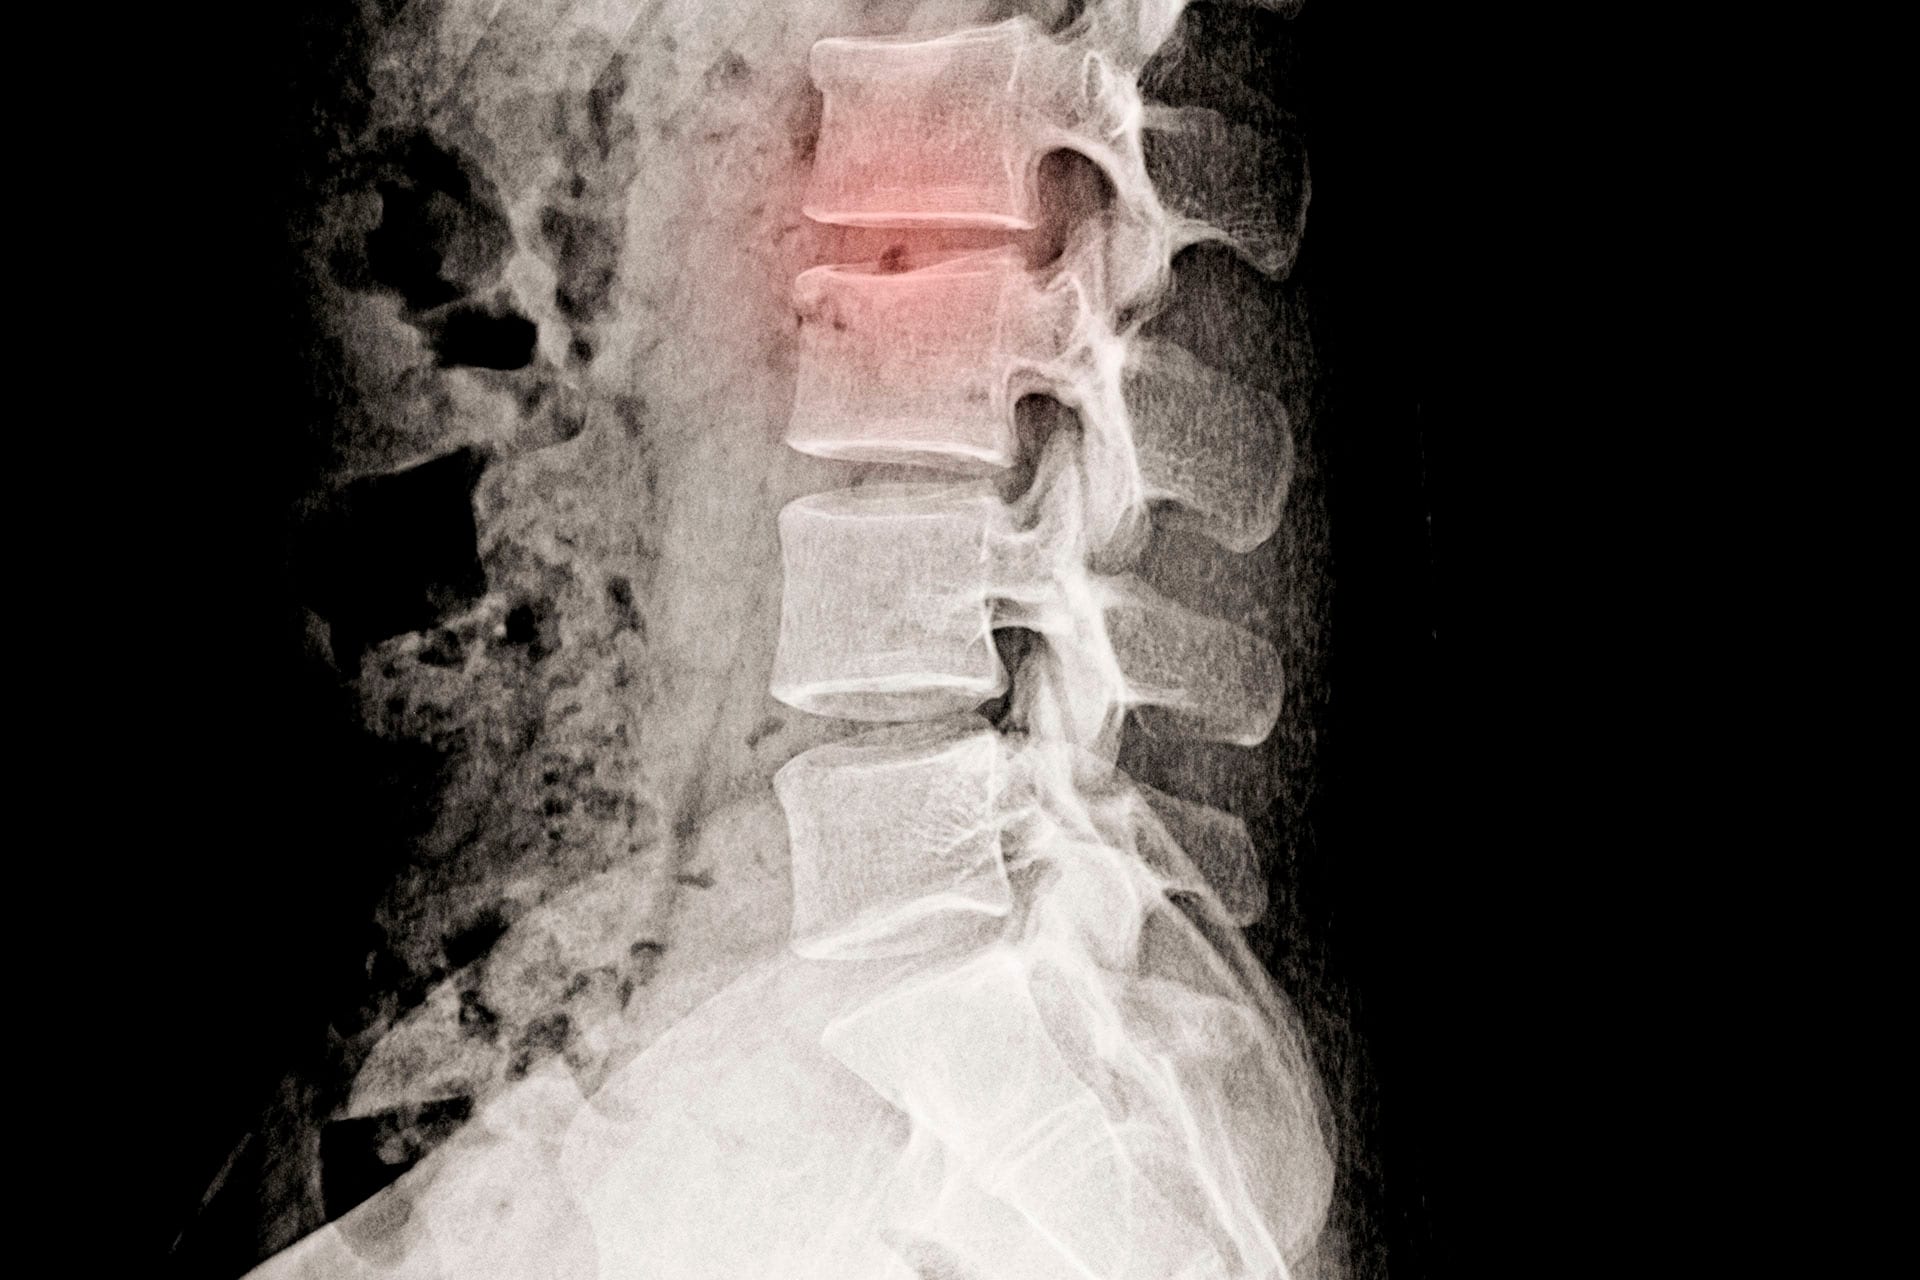

Fraturas vertebrais

As fraturas na coluna vertebral são bastante comuns. Ocorrem quando os ossos da…

7 Fatores associados à dor crônica na coluna

Dor na coluna é um dos sintomas mais comuns que existem. E é ainda mais preocupante…